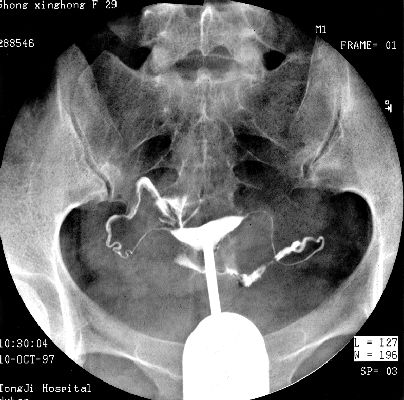

照片名称:子宫输卵管造影2

照片名称:子宫输卵管造影1

照片名称:子宫输卵管造影